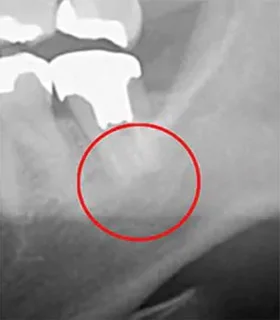

上記の画像は、「左」が3次元のCT画像で、「右」が2次元レントゲン画像です。左の赤丸がついている「黒い部分」が問題の箇所ですが、右の画像では黒く映っていません。CTであれば、はっきり確認できるため、治療すべき部位を見落とすリスクが下がります。